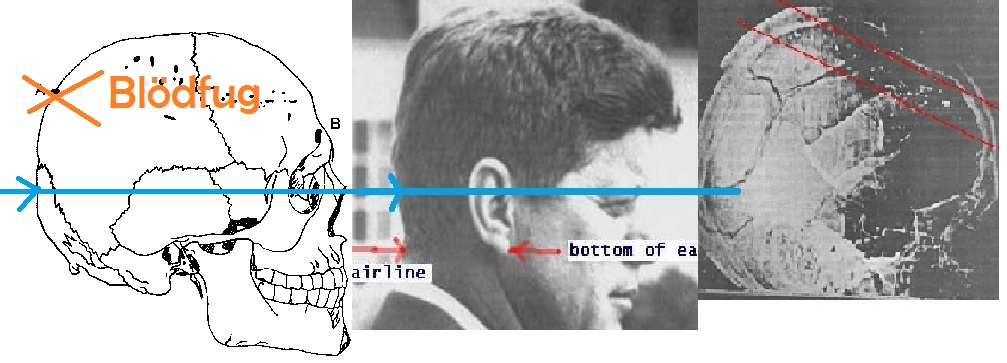

Massensuggestion. Weiter spricht für den Schuss von vorne (aus Richtung des Grashügels), dass dort stehende Passanten einen Schuss/mehrere Schüsse gehört haben (wollen). Dass sich so viele Menschen in genau diesem Moment geirrt haben sollen (aufgrund von Echos, Falschwahrnehmung, etc.) glaube ich einfach nicht.

BTW: Halte ich Dr. Cyril Wecht, der Kennedy u.A. auch autopsiert hat, für einen äußerst fähigen Menschen. Seine Aussagen, die die These des Schusses von vorn ebenfalls stützen, halte ich für

wissenschaftlich korrekt und verständlich wiedergegeben.